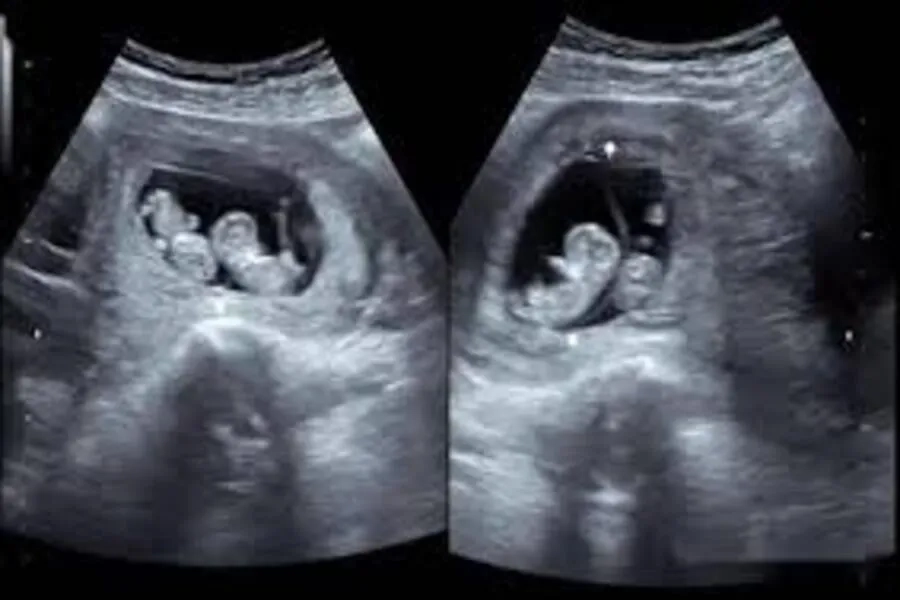

- Xác định số lượng thai trong buồng tử cung: nồng độ hormone tăng cao hơn mức bình thường ở giai đoạn đầu có thể gợi ý song thai hoặc đa thai. Tuy nhiên, cần thực hiện thêm siêu âm để xác nhận chắc chắn.

- Mang song thai hoặc đa thai, dẫn đến định lượng hormone được tạo ra nhiều hơn

Khi kết quả tăng cao bất thường, bác sĩ sẽ chỉ định siêu âm hoặc các xét nghiệm bổ sung để làm rõ nguyên nhân và đưa ra hướng theo dõi phù hợp.

Chỉ số nồng độ hormone tăng cao có thể là dấu hiệu của bầu song thai